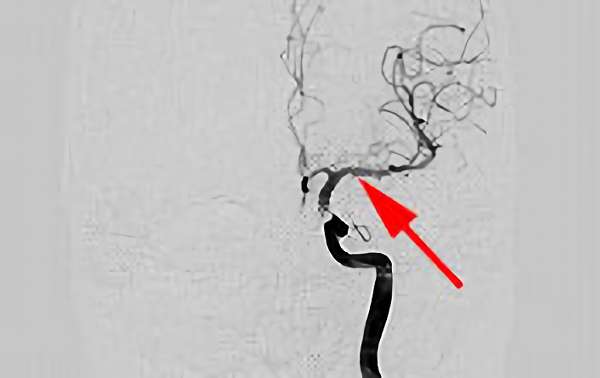

No.1583 手術前

No.1583 手術中

No.1583 手術後